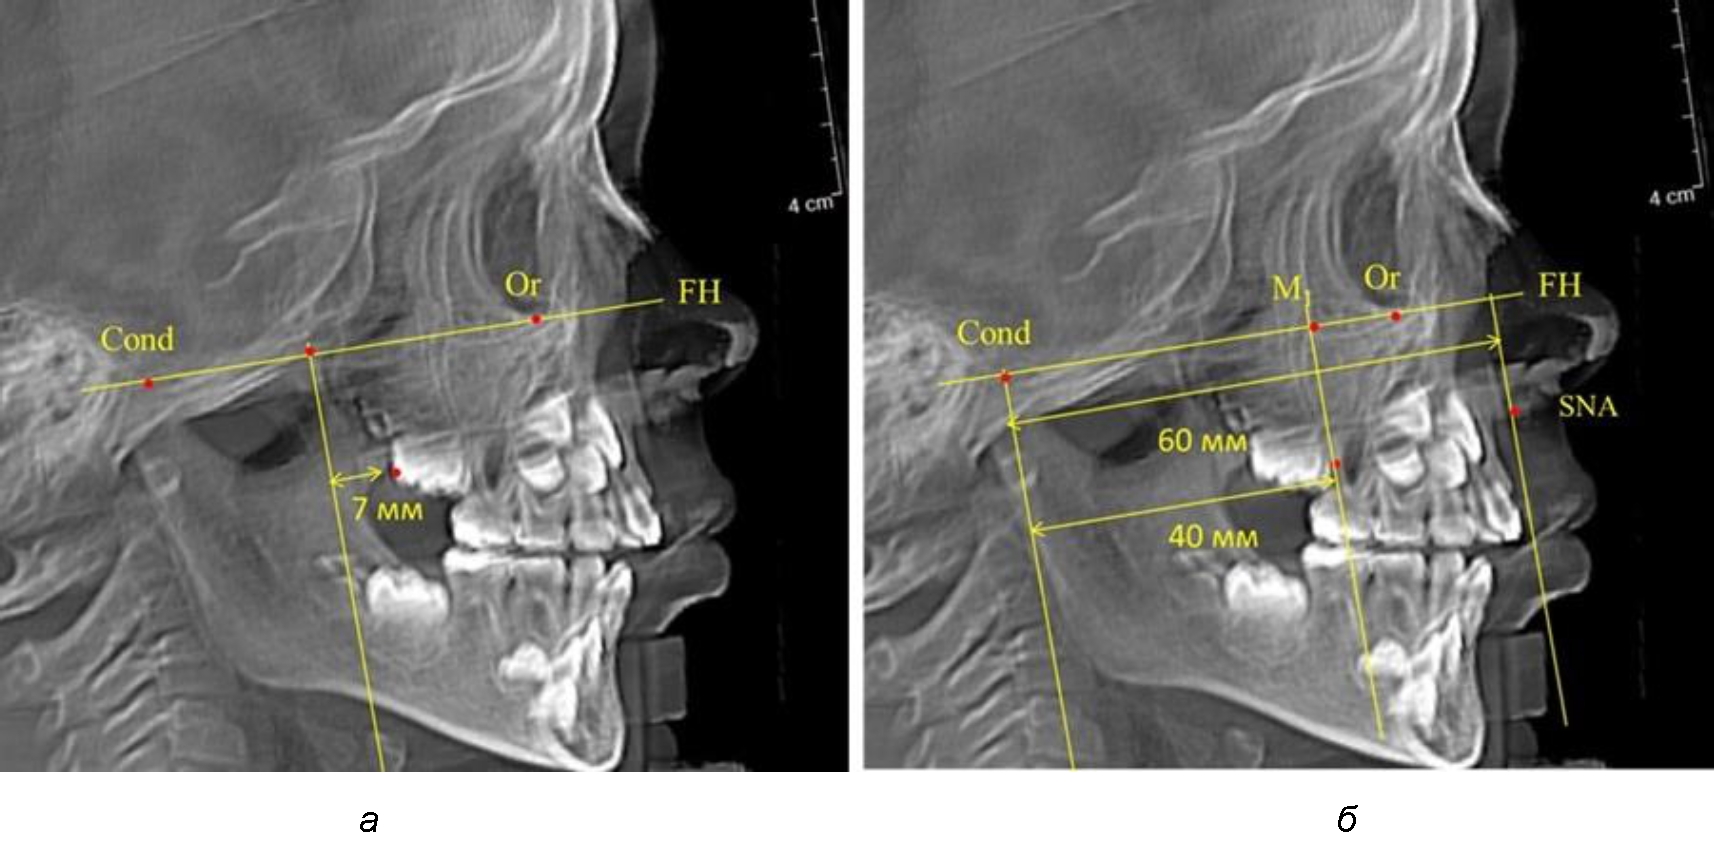

Второй частью исследования был анализ положения первых постоянных моляров в различные периоды сменного прикуса. На телерентгенограммах детей периода прикуса молочных зубов дистальная поверхность зачатка первого постоянного моляра отстояла от крыловидной вертикали на величину, составляющую около 7 мм, что было близким по значению к данным R. E. McDonald. Сагиттальный размер гантического отдела составлял около 60 мм, а его отношение к кондилярно-молярной глубине – 1,5 (рис. 4).

По мере роста челюстей увеличивалась глубина гнатического отдела лица, и кондиллярно-спинальный размер составлял в среднем (74,57 ± 0,93) мм. Дистальная поверхность первого постоянного моляра отстояла от крыловидной вертикали на величину, составляющую около 11 мм, что, так же, как и в периоде прикуса молочных зубов, было близким по значению к данным R. E. McDonald, а именно возраст, плюс 3 мм. Однако величина ошибки среднего значения свидетельствовала о вариабельности признака даже в восьмилетнем возрасте после замены передней группы зубов и установки ключевых постоянных моляров в окклюзионное равновесие. Обращает на себя внимание отношение глубины гнатического отдела лица к дистальному отделу, а именно к кондилярно-молярному расстоянию (рис. 5).

Рис. 4. Особенности положения первых моляров по R. E. McDonald (а) и по предложенному методу (б) у ребенка 4 лет

Рис. 5. Особенности положения первых моляров по R. E. McDonald (а) и по предложенному методу (б) у ребенка 8 лет